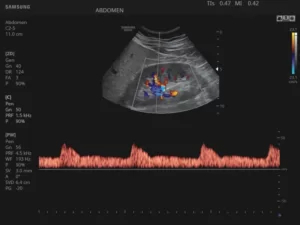

D-режим (допплерография)

Допплерография используется для неинвазивного изучения характеристик движения тканей и жидкостей в организме человека. Наибольшей информативностью этот формат сканирования обладает в диагностике сердечно-сосудистой и акушерско-гинекологической патологии.

Принцип работы режима основан на эффекте Доплера — физическом явлении, представляющем собой изменение частоты отраженного сигнала в зависимости от скорости движения изучаемого объекта. Частота увеличивается с приближением к датчику и снижается при удалении от него. В роли объектов, отражающих эховолны, обычно выступают эритроциты.

Благодаря D-режиму и его разновидностям можно исследовать основные параметры кровотока (направление, скорость, ламинарность), оценить степень васкуляризации патологического очага.

Сканирование, одновременно сочетающее одну из доплеровских методик и визуализацию в В-режиме, называется дуплексным. Оно позволяет получить комплексную информацию об анатомии сосуда (структуре его стенок, диаметре просвета), определить качественные и количественные характеристики гемодинамики. Кровоток, направленный к датчику, картируется оттенками красного цвета, от датчика — в синей цветовой палитре. Турбулентный кровоток отображается в сине-желто-зеленых тонах.

Триплексное сканирование — сочетание В-режима с двумя допплеровскими режимами (к примеру, спектральным и цветовым).

21.jpg

Рис.2. Почка в режимах CFI и PW.

Режим CFI (Color Doppler Imaging, ЦДК, цветовое допплеровское картирование)

Цветовой доплеровский режим позволяет анализировать характеристики кровотока не только в формате графика на осях, но и в виде цветной схемы. На ней красным цветом выделяются потоки крови, идущие по направлению к датчику, а синим — в противоположную от него сторону. Насыщенность оттенка свидетельствует о скорости движения эритроцитов: чем она ниже, тем ярче изображение.

23.jpg

Рис.3. Пуповина плода в режиме ЦДК + LumiFlow (программное обеспечение, устанавливаемое в ультразвуковом аппарате высокого разрешения).

Поскольку исследование в режиме CFI на большой области обладает ограниченной информативностью, спектральная доплерография предоставляет более детальные данные о небольшом участке, оба режима дополняют друг друга и в практической работе применяются совместно.

Режим PW (Pulsed Wave, спектральный, или импульсно-волновой)

В данном режиме ультразвук испускается сериями им­пульсов, которые, отразившись от эритроцитов, последовательно принимаются этим же датчиком. Также имеется воз­можность избирательного измерения скорости кровотока в отдельном сосуде.

Минусами PW-доплерографии являются невозможность исследования высоких скоростей потока в сосу­дах, расположенных на большой глубине, и вероятность искажения спектра скоростей течения жидкости, когда высокоскоростной кровоток ошибочно отображается как низко­скоростной.

28.jpg

Рис.4. Сердце плода в PW-режиме.